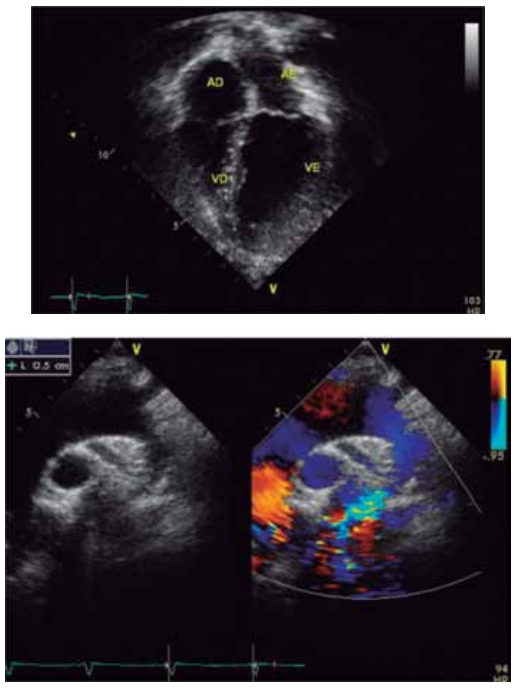

Analise a imagem a seguir.

Em face do exposto, assinale a alternativa que apresenta, corretamente, o diagnóstico e o tratamento preconizado.

A

Estenose de artéria pulmonar direita; angioplastia percutânea com colocação de

stent

.

B

Persistência do canal arterial; fechamento percutâneo com

plug

vascular.

C

Coarctação de aorta; aortoplastia cirúrgica em lactente.

D

Persistência da veia cava superior esquerda; conduta expectante.

E

Drenagem anômala de veias pulmonares total; correção cirúrgica total com reimplante do coletor em átrio esquerdo.